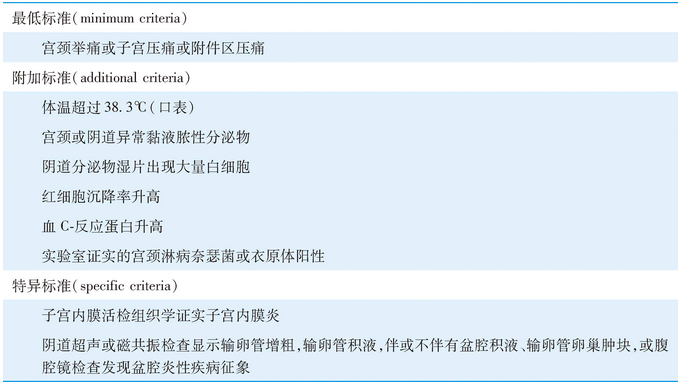

表20-1 盆腔炎性疾病的诊断标准(美国CDC诊断标准,2015年)

最低诊断标准提示在性活跃的年轻女性或者具有性传播疾病的高危人群,若出现下腹痛,并可排除其他引起下腹痛的原因,妇科检查符合最低诊断标准,即可给予经验性抗生素治疗。

附加标准可增加诊断的特异性,多数盆腔炎性疾病患者有宫颈黏液脓性分泌物,或阴道分泌物0.9%氯化钠溶液湿片中见到大量白细胞,若宫颈分泌物正常并且阴道分泌物镜下见不到白细胞,盆腔炎性疾病的诊断需慎重,应考虑其他引起腹痛的疾病。阴道分泌物检查还可同时发现阴道合并感染,如细菌性阴道病及滴虫阴道炎。

特异标准基本可诊断盆腔炎性疾病,但由于除B型超声检查外,均为有创检查或费用较高,特异标准仅适用于一些有选择的病例。腹腔镜诊断盆腔炎性疾病标准包括:①输卵管表面明显充血;②输卵管壁水肿;③输卵管伞端或浆膜面有脓性渗出物。腹腔镜诊断输卵管炎准确率高,并能直接采取感染部位的分泌物做细菌培养,但临床应用有一定局限性,如对轻度输卵管炎的诊断准确性较低、对单独存在的子宫内膜炎无诊断价值,因此并非所有怀疑盆腔炎性疾病的患者均需腹腔镜检查。